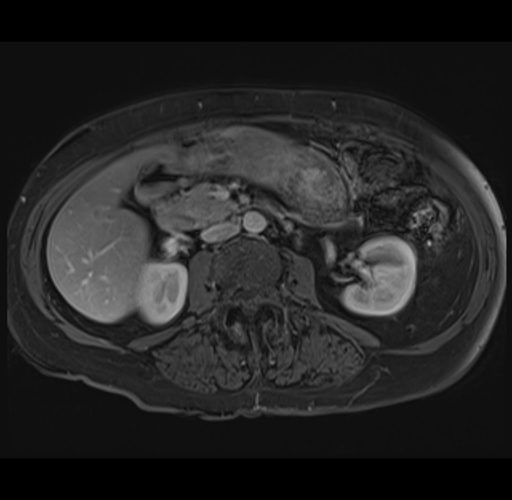

MRI T1

Imaging analysis

Based on your CT findings, which issue(s) would give reason for "planned slowing down moment(s)" in this case?

Considering a standard right hepatectomy procedure, what step(s) of the operation would you do differently in this case?